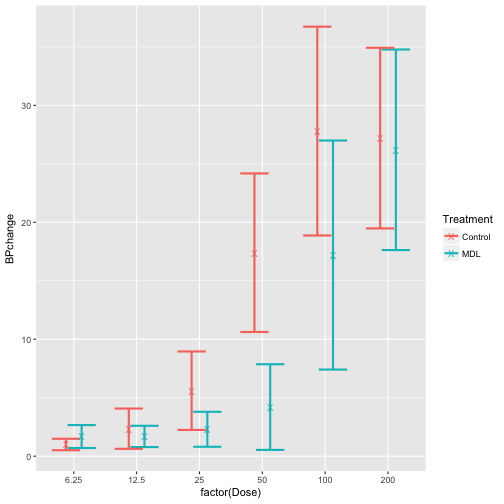

# create plot object BPchange vs. Dose using Rabbit dataset

p <- ggplot(Rabbit, aes(x = factor(Dose), y = BPchange, color = Treatment))

# take a look at the plot

p + geom_point(position = position_jitter(0.2))

# use stat_summary function to generate mean for each BPchange per Dose

p +

stat_summary(geom = 'point', fun.y = mean)

# examine mean_cl_normal function

mean_cl_normal(Rabbit$BPchange)

## y ymin ymax

## 1 11.21833 8.253206 14.18346

# assign position dodge function

posn.d <- position_dodge(width = 0.5)

# use stat_summary to generate confidence intervals of the mean

p + stat_summary(geom = 'errorbar', position = posn.d, fun.data = mean_cl_normal, size = 1) +

stat_summary(geom = 'point', position = posn.d, fun.y = mean, shape = "X", size = 3)